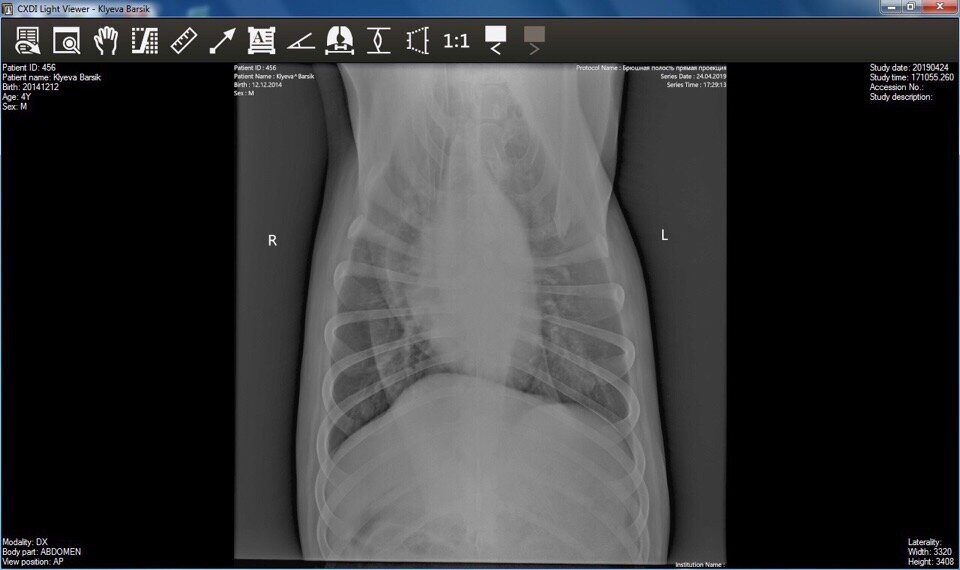

Одна из наиболее реализуемых целей для продолжения лечения Бархана была сделать новый рентген, про это мы уже говорили в статье: Пёс попал в надежные волонтеров, будем бороться!

Благодаря помощи добрых людей это получилось реализовать!

У собакина поставлен диагноз компрессия с Т5 до Т7 грудного позвонка. Логически был резкий удар, лопнули позвонки и образовалась костная мозоль, которая сжимает двигательный аппарат! Пёс Бархан: по извилистым тропам судьбы